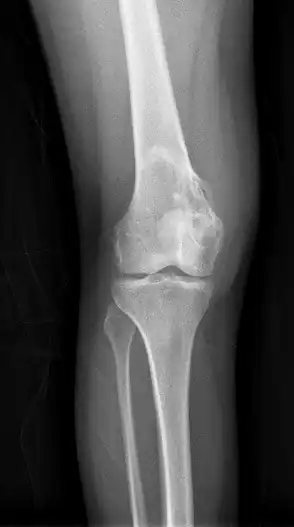

| Chondroblastoma[2] | ![]() | |